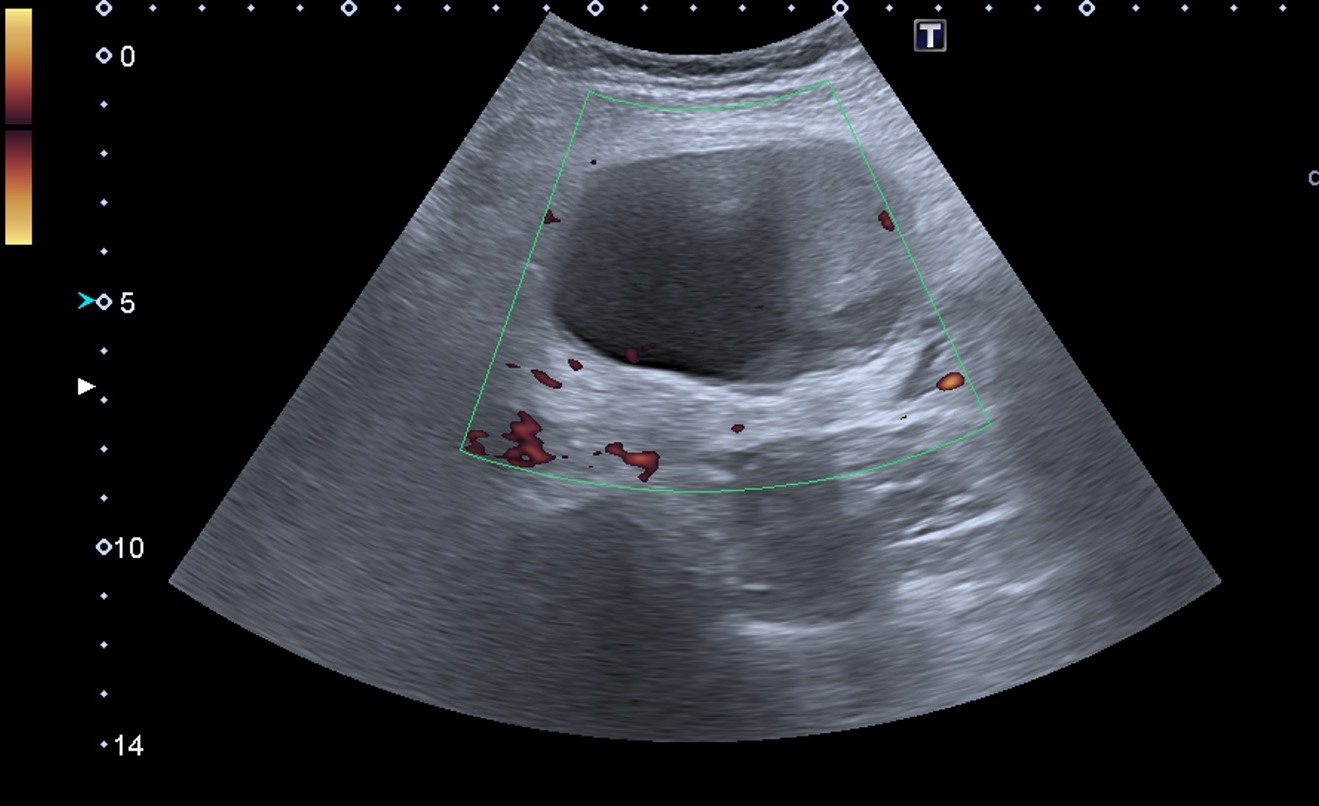

Hallazgos ecográficos

Ecografía abdominal en el Centro de Atención Primaria: lesión quística anecoica de 80 x 46 x 54 mm ubicada en mesogastrio. Quiste complejo de 30 x 30 mm, de paredes y septos engrosados, ubicado en polo superior del riñón izquierdo.

Juicio clínico: hallazgos de una lesión quística en mesogastrio y otra lesión quística compleja en el polo superior del riñón izquierdo.

Tomografía computarizada de abdomen: lesión quística en flanco izquierdo sin evidente dependencia con ningún órgano y de probable origen mesentérico o mesenquimal, posible linfangioma. Cambios inflamatorios periféricos y contenido heterogéneo post-sangrado. Quiste renal izquierdo Bosniak tipo III.

Resonancia magnética intestinal y renal: lesión mesentérica de 7,3 cm compatible con linfangioma quístico versus quiste dermoide. Quiste cortical en el polo superior del riñón izquierdo Bosniak III.